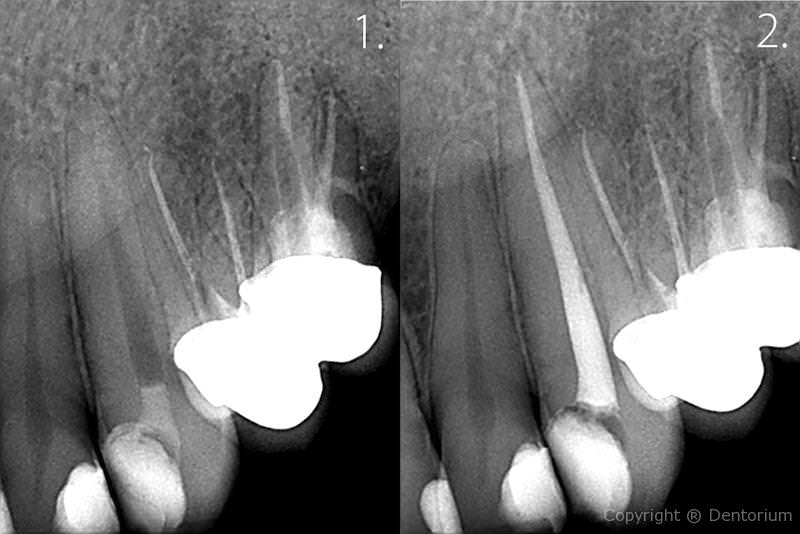

Il trattamento endodontico o trattamento canalare è necessario quando la polpa dentale è danneggiata dalle infezioni batteriche dalla carie o da trauma del dente.

- pulizia, allargamento e disinfezione del canale, somministrazione della medicina

- l’estrazione della medicina dentale, otturazione dei canali radicolari

- ricostruzione con il perno e otturazione dentale

Immediamente dopo il trattameneto si procede con RVG controllo del canale trattato.